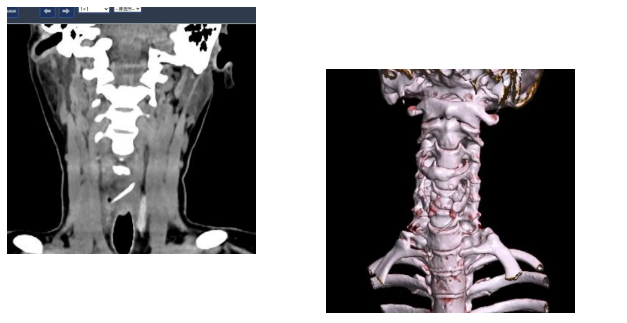

接诊的吕主任详细询问了陈女士的情况,结合她持续加重的咽痛,判断事情没那么简单。立即安排她进行双源CT检查并辅以三维重建技术。检查结果让所有人都捏了一把汗:一根近3公分长的鱼刺,深深卡在食管入口处,不仅位置刁钻,还已经刺穿食道,周围创面出现感染。